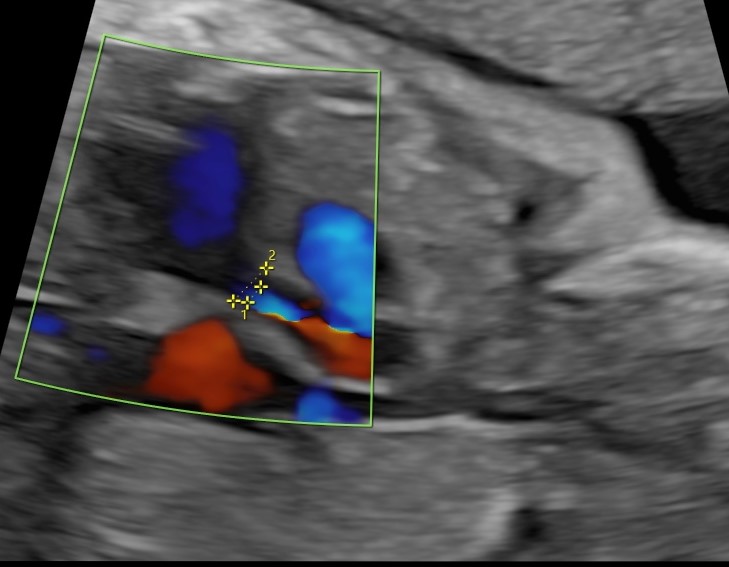

- Регистрировался двунаправленный поток в восходящей части и дуге аорты, трансмитральный поток имел монофазный характер, отмечался лево-правый сброс на овальном окне, а также двунаправленный поток в легочных венах.

По данным ультразвукового исследования после выполненной вальвулопластики клапана аорты и извлечения баллона с иглой отмечается увеличение эффективного отверстия клапана аорты и отсутствие жидкости в полости перикарда.

Через 12 часов после операции было проведено ультразвуковое исследование сердца плода. Фракция выброса ЛЖ увеличилась до 24 %, диаметр эффективного отверстия АК составил 2,9 мм. Максимальный градиент на АК возрос до 21 mm Hg, митральная регургитация уменьшилась с тотальной до 2 степени. Жидкости в полости перикарда обнаружено не было.